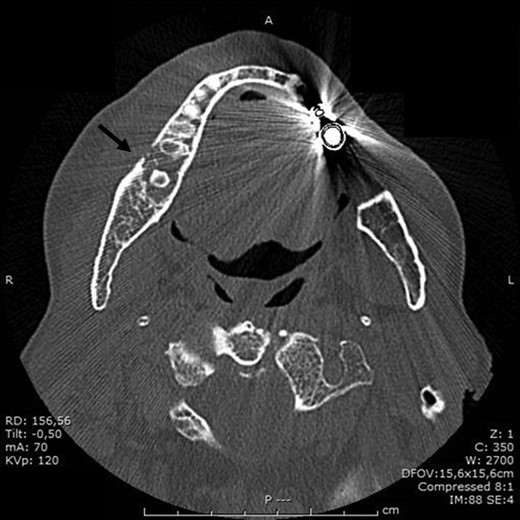

BRONJ was clinically diagnosed at the patient’s first visit based on her history and was confirmed radiologically by the dental x-ray and CT performed in July 2016. X-rays showed reduced density of the alveolar bone edges, particularly on the right where the alveolar bone crest profile was rather irregular. A small residual root was present in the molar region on the right. The inferior alveolar nerve canal was clearly recognizable, on both sides.

In the light of these results, it was decided in September 2016 that the patient should undergo major surgery involving mandibular bone curettage and positioning of HAM (Fig. 1).

In November 2016, the patient underwent surgery under general anaesthesia. After infiltration of a local anaesthetic (mepivacaine + adrenaline 1:200 000), surgery was carried out as described: mucoperiosteal incision of the right mandible with mesial and distal drainage, extensive fistulectomy of the hyperplastic mucose membrane, which showed multiple fistulas, skeletonisation and exposure of abundant necrotic tissue; debridement of hyperplastic-inflammatory tissue and ostectomy of necrotic bone with osteoplasty of sharp edges; positioning of HAM and water and hermetic suture with Polisorb 3/0 absorbable braided thread (Fig. 2A–E). Histological examination confirmed the presence of inflammation and the diagnosis of osteonecrosis. The mesial and distal bone curettage margins were dictated by the x-ray images (Fig. 3) identifying above all the radio-opaque areas, often associated with a periosteal reaction, as well as by the need to remove any bone sequestra present. The imaging was also associated with the intraoperative assessment of the macroscopic appearance of the bone and in particular the signs of bleeding from the cortex and medulla. The HAM was 3 × 3 cm2 in size and was positioned over the curetted area and under the mucosal flap.